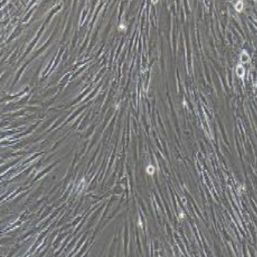

形态特性:长梭形

生长特性:贴壁培养

3) 细胞生长方式:长梭形,贴壁培养。